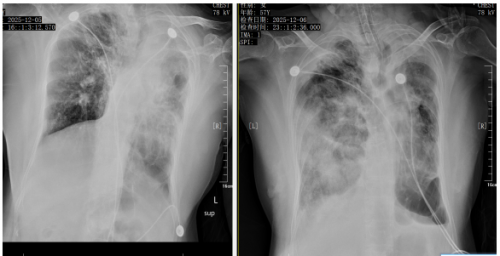

胸片可见双肺炎性渗出。

12月5日 12月6日

病程第二日,患者病情骤然进展,呼吸费力,呼吸性酸中毒进行性加重,先后予以经鼻高流速吸氧、无创呼吸机辅助通气,后因患者氧合进行性下降,意识进行性变差,复查血气+离子示呼吸性酸中毒合并代谢性酸中毒、高钾血症,同时征得家属同意后,立即行经口气管插管呼吸机辅助通气。

后患者病情持续进展,氧合指数<100mmHg,胸片可见肺部感染进行性加重,SOFA评分13分,“重症肺炎”、“ARDS”、“脓毒血症”诊断明确。